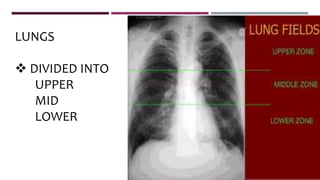

LUNGS

 DIVIDED INTO

UPPER

MID

LOWER